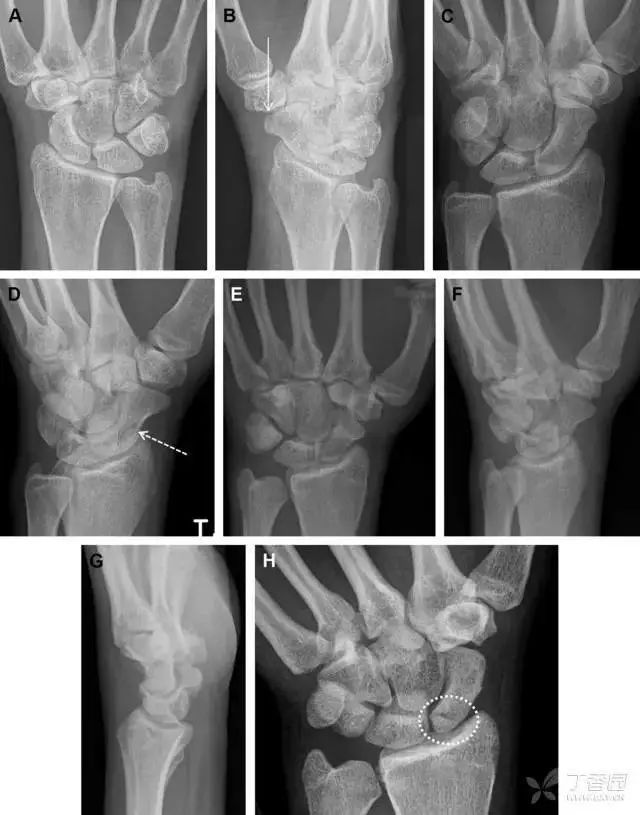

图 1 57 岁女性,摔倒后手掌撑地,桡骨茎突压痛。(A~C)前后位、斜位、侧位片示软组织肿胀(*)和发丝样骨折(白色箭头);(D~F)2 周后,前后位、斜位、侧位片示骨折线显明,由于新骨痂沉积而呈现透亮线与硬化线并存;(G~I)另一患者,桡骨茎突骨折在前后位及侧位片上显示不明显,而在斜位片显示更清楚。

舟状骨骨折

舟状骨骨折 60%~70% 发生于腰部,15% 发生于近极, 10% 发生于远极, 8% 发生于远端关节面。除了常规的前后位、侧位、斜位片外,还需要拍专门的舟状骨位片(腕关节尺偏,以舟状骨为中心的腕关节前后位片),特别是鼻烟壶有压痛时。

图 2 舟状骨骨折 (A、B)第 1 例患者,舟状骨远极关节内骨折(白色箭头),斜位片显示较清楚(B);(C、D)第 2 例患者,舟状骨腰部骨折(虚线箭头),斜位片显示较清楚(D);(E~H)第 3 例患者,舟状骨近极骨折,常规 X 线片均未看到骨折,而在舟状骨位片上才能见到骨折(虚线圆)。